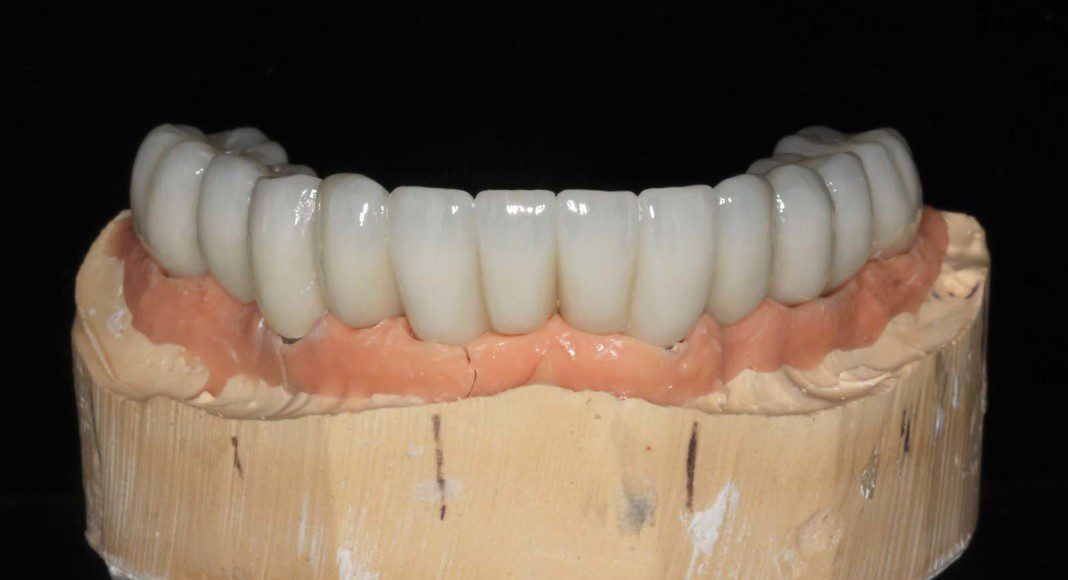

Once everyone is satisfied, we can send the wax-up to the lab for scanning, milling and customization. Here is the upper, zirconia bridge on the master cast (frontal view).

Frontal view, master cast with tissue moulage (simulated gum tissue). Because this material can be modified, we modify it to guide the tissue contours beyond what we did in with the temporary bridges.

Occlusal view, master cast with tissue moulage (simulated gum tissue). Because this material can be modified, we modify it to guide the tissue contours beyond what we did in with the temporary bridges.

The intaglio (tissue side) of the lower, zirconia bridge. The contours are “convex” not concave for easy hygiene.